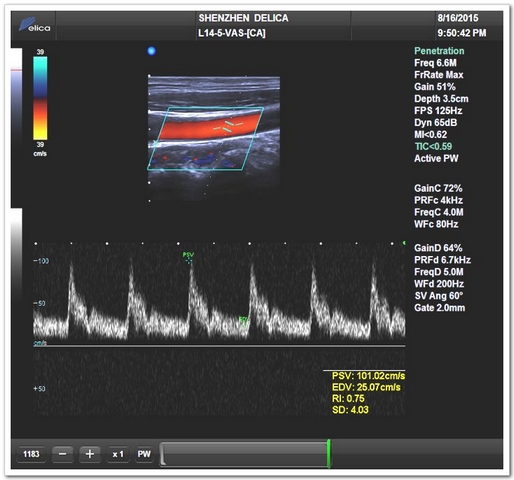

彩超模式(頸總動(dòng)脈)

彩超模式(椎動(dòng)脈)